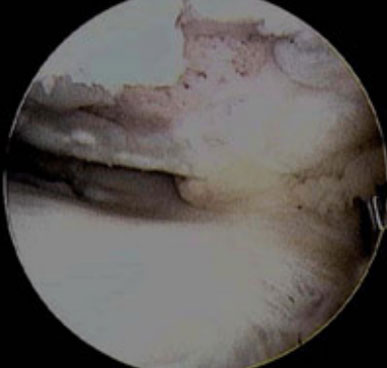

Hình ảnh MRI cho thấy DCCT đứt hoàn toàn. Các sợi DCCT đã bị đứt và DCCT có hình dạng gợn sóng [vị trí mũi tên vàng].